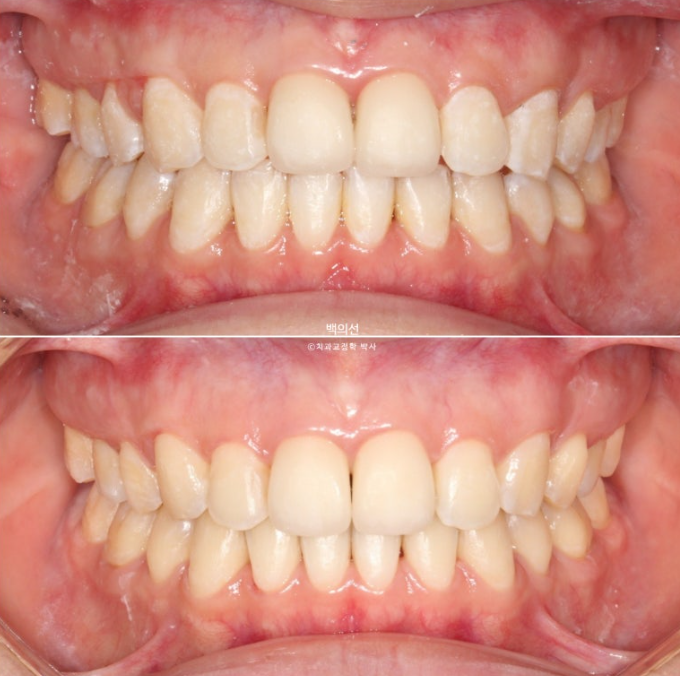

25.02~25.07

이제 전후 비교 보겠습니다.

총 치료기간은 4개월입니다.

25.07

기울어져 보이던 측절치는 대칭성을 회복했으며

교합은 처음보다 좋아졌습니다.